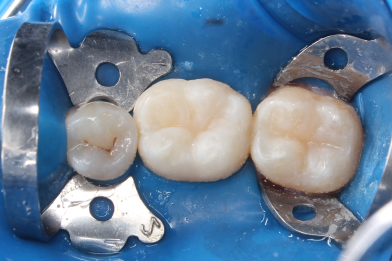

Лечение среднего кариеса зубов 2.6, 2.5,2.4. Функциональная и эстетическая реставрация

Эвинян Лусине Артоевна -